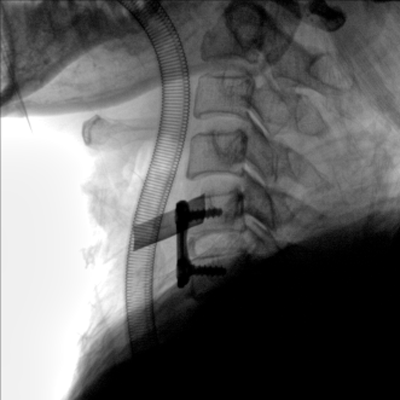

大尺寸動(dòng)態(tài)平板探測(cè)器,高DQE、低噪聲、圖像清晰。采用多分辨率圖像增強(qiáng)處理技術(shù),不同部位不同圖像處理算法,滿足客戶多樣化的需求。

圖形化操控界面設(shè)計(jì):設(shè)有多種人體特征攝影參數(shù),操作簡(jiǎn)便。雙向紅光十字定位系統(tǒng):實(shí)現(xiàn)無射線下的高效定位。信息共享:遵循DICOM3.0格式接口,可無縫對(duì)接云PACS系統(tǒng)。